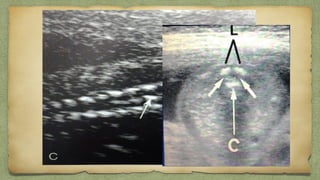

๏ฑ Occupy 1/3 โ€“ ยฝ of thorax

๏ฑ Cardiac position & situs is

Imp

๏ƒผ Apex points toward Lt

๏ƒผ Lt atr close to spine

๏ƒผ Rt Vent close to chest wall

HEART

๏ฑ 2 ventricles/ walls of equal size

๏ฑ 2 atria / walls of equal size

๏ฑ Foramen ovale moving in left atrium

๏ฑ Pulmonary veins entering left atrium

๏ฑ Motion of mitral valves (left side) regular

๏ฑ Motion of tricuspid valves (right side) regular

๏ฑ Continuity of interventri septum

Check at a Glance